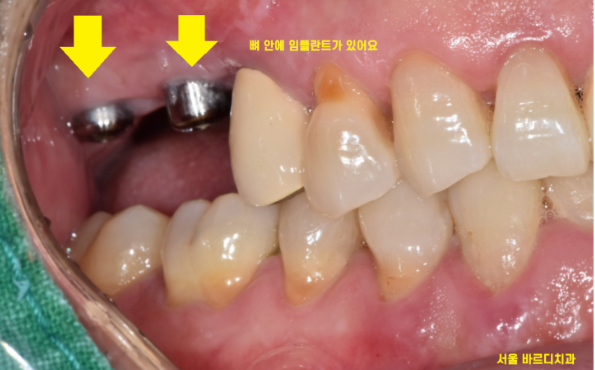

뼈가 거의 없는 경우에는

임플란트를 잇몸 안에 묻어두기도 하는데요.

이럴 경우에는 잇몸밖에 안느껴지기 때문에

임플란트 심은게 맞나.. 싶기도 합니다.

겉으로 봤을 때는 잇몸만 느껴지지만

x-ray를 보실까요~?

임플란트가 잘 심어져있습니다.

이럴 경우 잇몸 밖으로 나사를 연결하는

2차 수술을 진행해야 하는데..